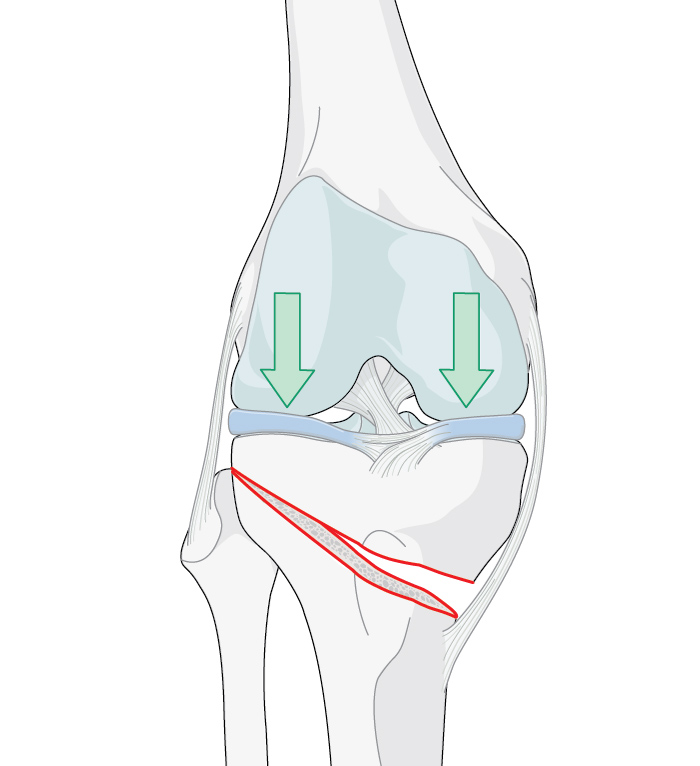

Figure 2. Arrows indicate the load distribution before (left) and after (center) the procedure (medial open wedge osteotomy with locked plate osteosynthesis)(right). Used under CC BY-SA 3.0 de license. Source. Image (right) by J Lengerke.

A wedge-shaped cut (see Figure 1) is made in the top of the tibia to change the alignment of the knee by shifting the weight/loading of the arthritic part of the joint to the healthier part (see Figure 2) [12]. It is mostly performed for varus deformities, less commonly for valgus deformities [13]. Preoperative planning using imaging helps surgeons to calculate the size of the wedge/osteotomy needed to correct the weight-bearing axis (see Figure 3). For best results, it is critical that correct alignment is achieved [14]. There is controversy around what constitutes the ideal mechanical alignment but generally the recommended alignment range is between 2° and 6° of mechanical valgus [15].